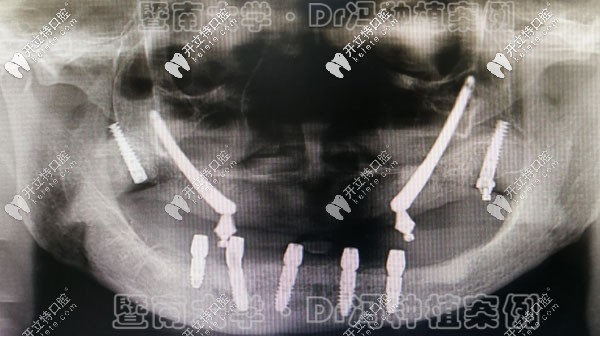

馮智強分院院長 擅長領(lǐng)域:尤其是對全口無牙頜的種植修復(fù)有較豐富的臨床經(jīng)驗;

李詠旭 擅長領(lǐng)域:數(shù)字化導(dǎo)板種植技術(shù)、All-on-4種植技術(shù)等;

劉志昕 擅長領(lǐng)域:ICOI微創(chuàng)種植牙、ALL-ON-4種植牙、GBR植骨術(shù)、 onlay植骨等口腔修復(fù);

趙清桐 擅長領(lǐng)域:全口復(fù)雜牙種植術(shù)、復(fù)雜牙微創(chuàng)拔除、牙周病治療、牙周外科等;

張春雷 擅長領(lǐng)域:微創(chuàng)種植修復(fù)、復(fù)雜疑難病例的種植修復(fù)等;